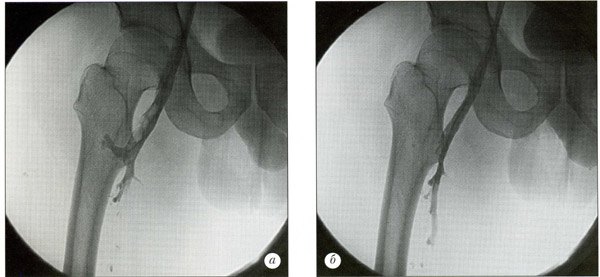

6. Флебография.

Диагностика острого венозного тромбоза в амбулаторных и в стационарных условиях базируется на оценке клинической симптоматики и результатах инструментальных методов обследования и должна осуществляться в кратчайшие сроки поскольку от быстроты определения самого факта тромбоза, его локализации, характера проксимальной части тромба зависит клинический прогноз. Во всех случаях острого венозного тромбоза обследование предпочтительно начинать с ультразвукового ангиосканирования и лишь тогда, когда визуализация затруднена (например, подвздошно-кавального сегмента) или в тех случаях, когда при наличии клиники илиофеморального флеботромбоза осуществить верификацию диагноза неинвазивно невозможно показано выполнение в экстренном порядке рентгеноконтрастного исследования. Скрининговым методом диагностики острого венозного тромбоза стал на сегодняшний день тест на Д-димер. Отрицательный его результат исключает венозный тромбоз с вероятностью 95-98% у пациентов с низким риском его возникновения.